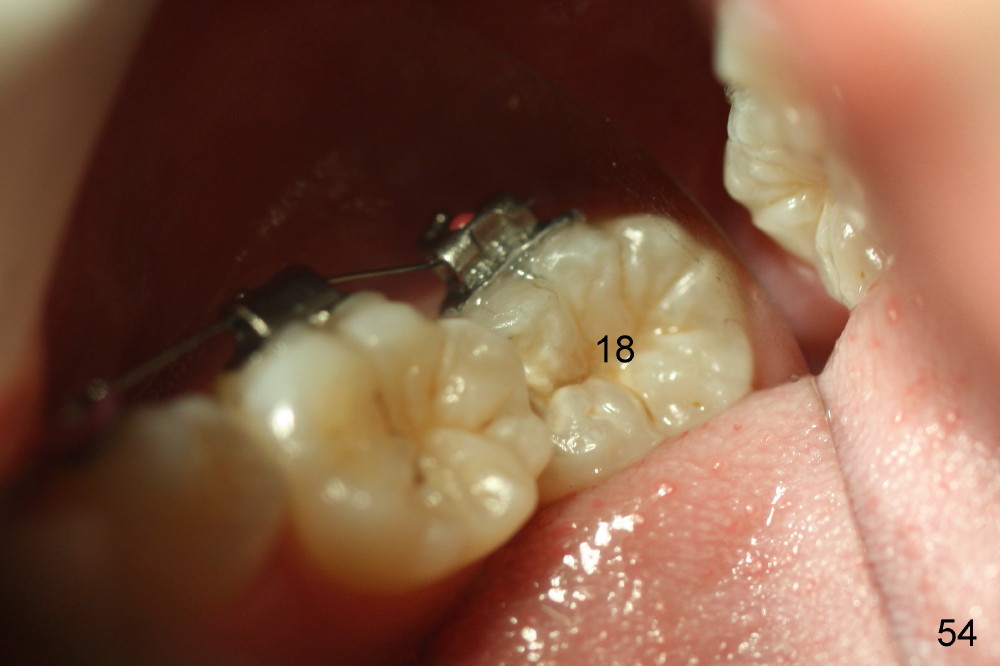

Two months later, LL7 (#18 in Fig.53,54) appears to be uprighted by itself (probably due to mesialization of the teeth mesial to it); a bracket is placed with .012 niti wire. No power chains are used to close the diastemata among the upper teeth, since the anterior overjet is minimal. A rotation wedge is placed in the distal wings of #27 to fix rotation. Is it right?